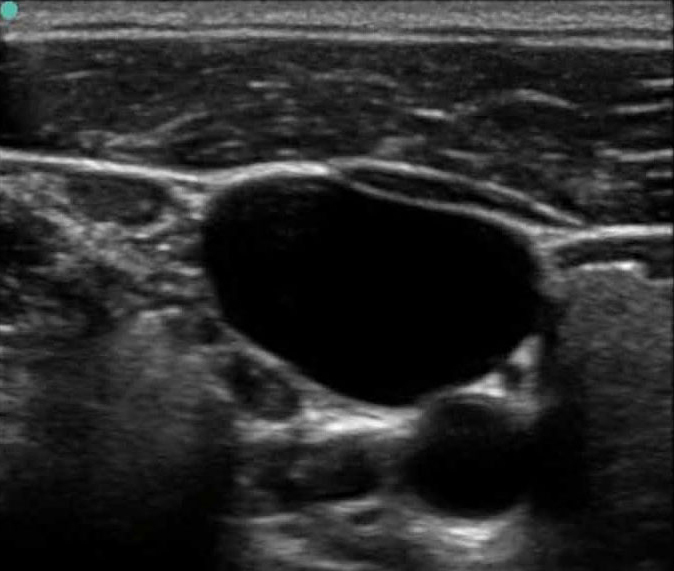

Vascular Access 2 Image

M-Turbo: IJV Short Axis 2